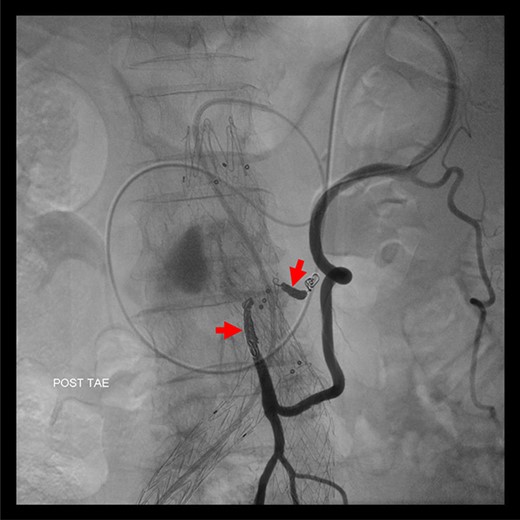

Angiography for decision-making revealed a type II endoleak from the IMA to the AAA, but no other visible endoleak (Fig. 2). Based on these findings, we planned additional EVAR for left CIAA, which was thought to have enlarged in natural course, and IMA embolization for the type II endoleak associated with sac enlargement. A staged strategy was devised. IMA embolization was planned several days after EVAR. Sac angiography from the IMA via Riolan’s arcade showed a flow-through endoleak to the ARA as a drainage artery (Fig. 3). Based on this finding, we embolized the ARA and the IMA with coils via Riolan’s arcade (Fig. 4). Selection and embolization of the drainage artery were technically feasible because of the flow from the IMA to the ARA. No deterioration of renal function due to ARA embolization was observed. One year after treatment, a CT scan demonstrated that the sac shrank to 42 mm with no evidence of a continuing endoleak (Fig. 5).

Coil embolization of the IMA and ARA was performed successfully via Riolan’s arcade.